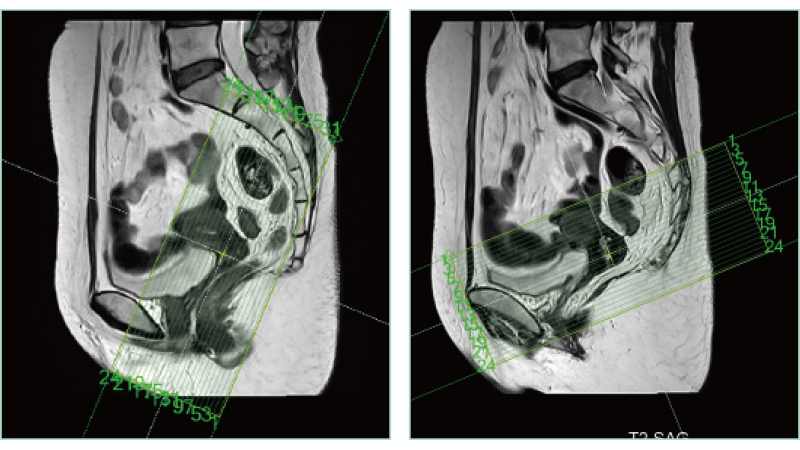

AutoPose FemalePelvis

The slice line setting support function, "AutoPose," automatically sets the slice lines as soon as the scanogram is scanned.